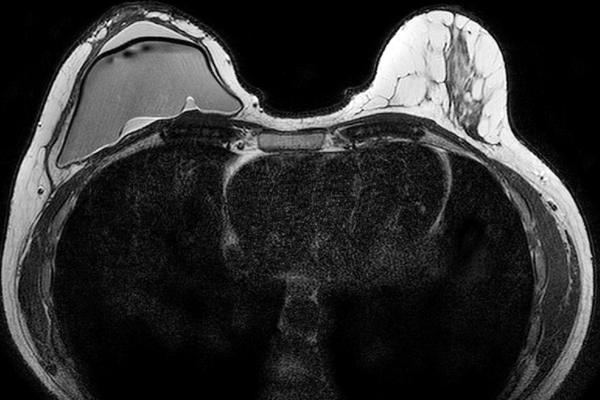

Heterotopic ossification (HO) is a well-known complication following total hip arthroplasty (THA), with an average incidence of 30%. Patients are classified according ...